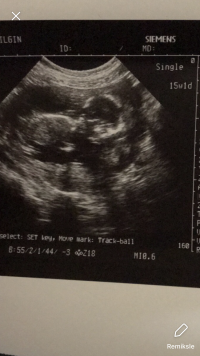

Merhaba 15+1 doktorun söylemedi cinsiyeti tahmin istedim onuda söylemedi 🙁 tahmin yapabilen varmı acaba devlet hastanesine gidiyorum özele gitsem söylerlermi 12 öğrenen çok insan var 12+2 söylemedi

Merhaba yüklemiş olduğunuz görselde nub çıkıntısı görülmüyor bu nedenle bebeğinizin cinsiyeti hakkın da tahminde bulunamıyoruz. 16-17 ve 20. haftalarda bebeğinizin cinsiyetini net olarak öğrenebilirsiniz. Biraz daha sabırlı olun . Sağlıklı gebelik geçirmeniz dileği ile.